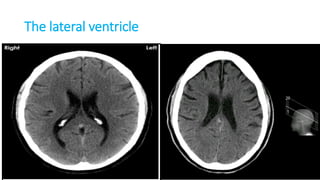

THE VENTRICLES

Ventricles

• Lateral ventricle

• Frontal horn

• Occipital horn

• Temporal horn

• Third ventricle

• Fourth ventricle

• Central canal

Foramen monoro

Aqueduct of Silvius

Interventricular foramina

(or foramina of monro)

The lateral ventricle

The frontal horn

The

occipital

horn

The temporal horn

The 3rd ventricle

The 4th ventricle

Foramen Luschka and Magendie